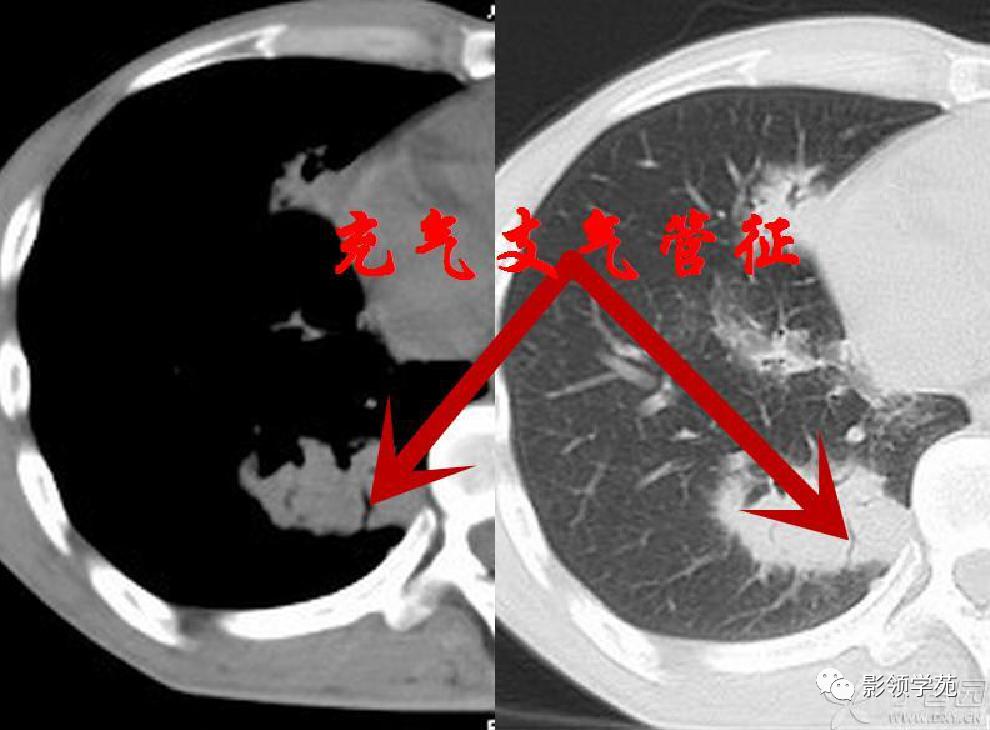

胸部CT检查有阳性发现者占97%,包括多发性肺结节、肿块、楔形病灶、片状浸润阴影、空洞、气道狭窄或溃疡、肺出血等。肺部Wegener肉芽肿CT征象多样,典型的影像学特点是“三多”,即多发性、多样性、多变性。多发性指肺内多处病变,散在双侧肺野,尤以双下肺好发。多样性指病变形态及新旧不一,病变形态多样,呈结节、实变、空洞及条索影等,结节及空洞较为常见。空洞形成是Wegener的重要影像特点,环形空洞是此病的特征。浸润、空洞及结节等多种形式常同时存在。多变性指病变部位、大小及形态处于动态变化之中。

肺内多发结节和肿块是肺Wegener肉芽肿最常见的影像征象,表现为两肺散在分布、多发大小不等类圆形结节或肿块影,以两肺中下野分布多见。部分结节和肿块内可见空洞,洞壁多较厚,内缘光滑或不规则,空洞呈边缘性强化。合并感染时空洞内可形成液-气平面。结节或肿块周围一般都有较短毛刺,部分病灶有长毛刺与邻近的胸膜相连,表现为胸膜凹陷征。这与病理上结节周围存在大量成纤维细胞以及以纤维化形式愈合有关。

病例3:双肺多发结节伴空洞,部分空洞见气液平面。